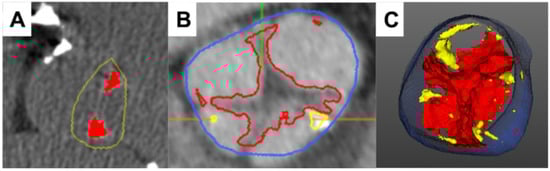

- Grodecki, K.; Tamarappoo, B.K.; Huczek, Z.; Jedrzejczyk, S.; Cadet, S.; Kwiecinski, J.; Rymuza, B.; Parma, R.; Olasinska-Wisniewska, A.; Fijalkowska, J.; et al. Non-calcific aortic tissue quantified from computed tomography angiography improves diagnosis and prognostication of patients referred for transcatheter aortic valve implantation. Eur. Heart J. Cardiovasc. Imaging 2021, 22, 626–635. [Google Scholar] [CrossRef]